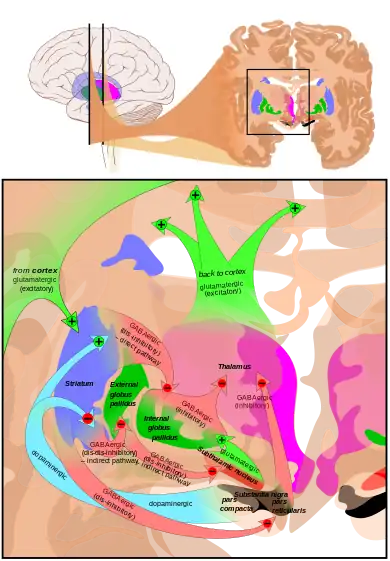

Basal ganglia

The largest and most important sources of dopamine in the vertebrate brain are the substantia nigra and ventral tegmental area.[42] Both structures are components of the midbrain, closely related to each other and functionally similar in many respects.[42] The largest component of the basal ganglia is the striatum.[52] The substantia nigra sends a dopaminergic projection to the dorsal striatum, while the ventral tegmental area sends a similar type of dopaminergic projection to the ventral striatum.[42]

Progress in understanding the functions of the basal ganglia has been slow.[52] The most popular hypotheses, broadly stated, propose that the basal ganglia play a central role in action selection.[53] The action selection theory in its simplest form proposes that when a person or animal is in a situation where several behaviors are possible, activity in the basal ganglia determines which of them is executed, by releasing that response from inhibition while continuing to inhibit other motor systems that if activated would generate competing behaviors.[54] Thus the basal ganglia, in this concept, are responsible for initiating behaviors, but not for determining the details of how they are carried out. In other words, they essentially form a decision-making system.[54]

The basal ganglia can be divided into several sectors, and each is involved in controlling particular types of actions.[55] The ventral sector of the basal ganglia (containing the ventral striatum and ventral tegmental area) operates at the highest level of the hierarchy, selecting actions at the whole-organism level.[54] The dorsal sectors (containing the dorsal striatum and substantia nigra) operate at lower levels, selecting the specific muscles and movements that are used to implement a given behavior pattern.[55]

Dopamine contributes to the action selection process in at least two important ways. First, it sets the "threshold" for initiating actions.[53] The higher the level of dopamine activity, the lower the impetus required to evoke a given behavior.[53] As a consequence, high levels of dopamine lead to high levels of motor activity and impulsive behavior; low levels of dopamine lead to torpor and slowed reactions.[53] Parkinson's disease, in which dopamine levels in the substantia nigra circuit are greatly reduced, is characterized by stiffness and difficulty initiating movement—however, when people with the disease are confronted with strong stimuli such as a serious threat, their reactions can be as vigorous as those of a healthy person.[56] In the opposite direction, drugs that increase dopamine release, such as cocaine or amphetamine, can produce heightened levels of activity, including, at the extreme, psychomotor agitation and stereotyped movements.[57]

The second important effect of dopamine is as a "teaching" signal.[53] When an action is followed by an increase in dopamine activity, the basal ganglia circuit is altered in a way that makes the same response easier to evoke when similar situations arise in the future.[53] This is a form of operant conditioning, in which dopamine plays the role of a reward signal.[54]